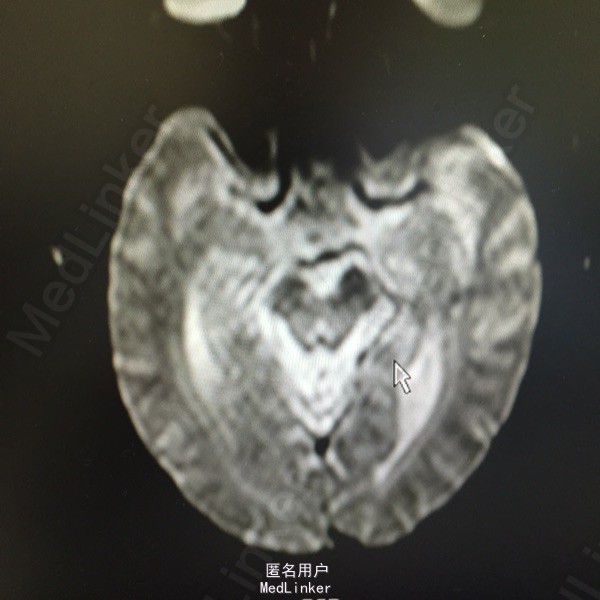

头痛伴视物双影5天。既往高血压、糖尿病、脑梗死。该患于入院前5日无明显诱因出现视物双影,偶伴头痛,不伴有恶心、呕吐,无视物旋转,无吞咽困难,病程中无肢体活动障碍,无言语不清,无意识障碍及尿便失禁。曾有中耳炎病史,伴有听力减退,曾于入院前3日在眼科医院激光治疗眼底出血。为求进一步诊治而来我院。

查体:神清语利,左眼内收受限,鼻唇沟对称,伸舌居中,双耳听力减退,肌力肌张力正常,双下肢病理症(-)颈强(-)。

诊断:脑梗死、高血压、2型糖尿病、高脂血症、中耳炎 治疗:营养神经、改善循环、神经生长因子、降脂、抗炎对症治疗。